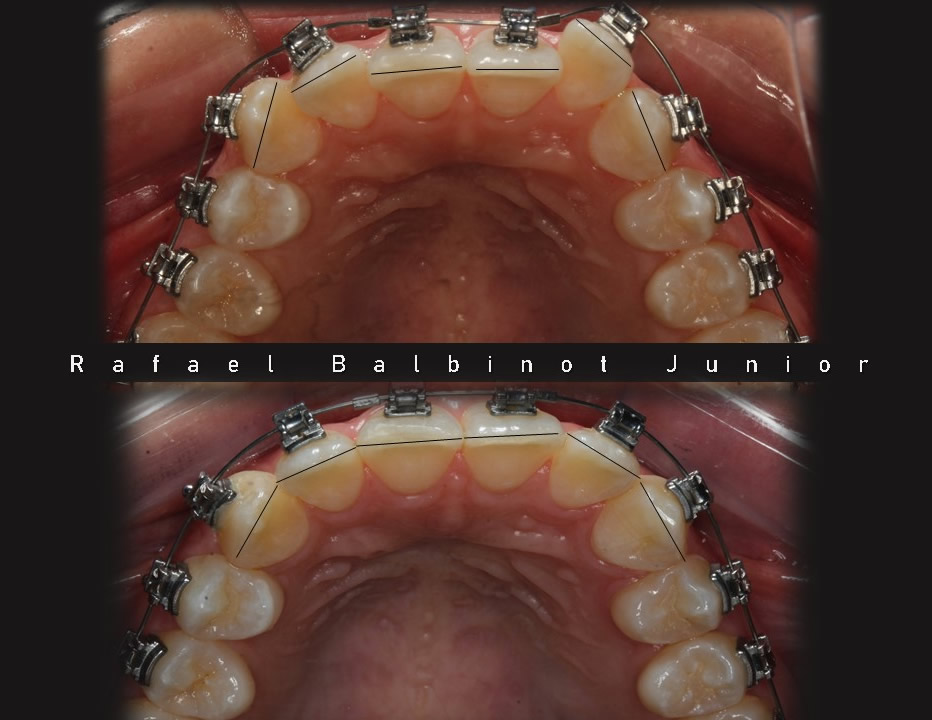

A Ortodontia é a especialidade que trata o mau posicionamento dos dentes e/ou das arcadas dentárias. Dentes tortos e fora da posição correta prejudicam de forma significativa a estética, a harmonia do sorriso e a função mastigatória. Confira os sorrisos transformados pelo Instituto Balbinot.